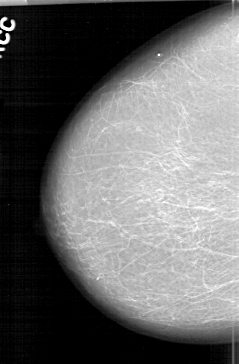

D_4194_1.LEFT_MLO

LEFT_CC LINES 6466 PIXELS_PER_LINE 4111 BITS_PER_PIXEL 12 RESOLUTION 43.5 OVERLAY

FILE: D_4194_1.LEFT_CC.OVERLAY

TOTAL_ABNORMALITIES 1

ABNORMALITY 1

LESION_TYPE CALCIFICATION TYPE PLEOMORPHIC DISTRIBUTION SEGMENTAL

ASSESSMENT 0

SUBTLETY 4

PATHOLOGY BENIGN

TOTAL_OUTLINES 1

BOUNDARY